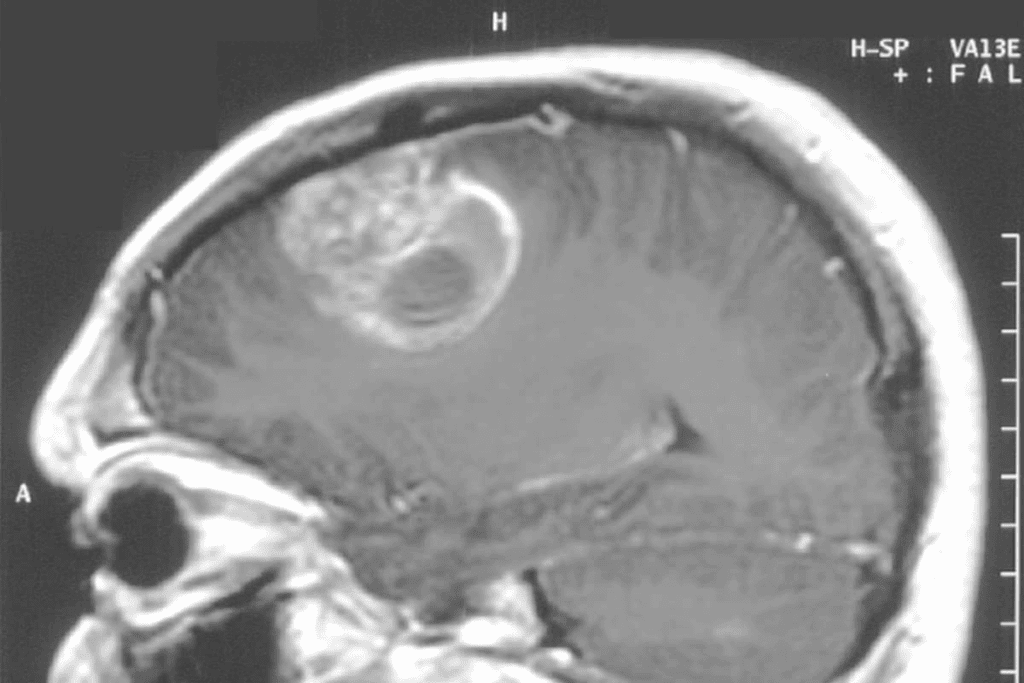

MRI Scans: The Gold Standard for Brain Tumor Diagnosis

MRI scans are the top choice for finding brain tumors in kids. They can spot tumors and normal brain tissue with great accuracy. This tool has changed how we look at brain tumors in kids, helping doctors plan better treatments.

What Brain Tumors Look Like on MRI

Brain tumors look different on MRI scans. It depends on the tumor’s type, size, and where it is. Tumors show up as abnormal masses with special features.

For example, some tumors might look bright on certain images. This helps doctors see how big the tumor is and where it is in relation to other parts of the brain.

Some tumors might look:

- Bright on T2-weighted images because they have a lot of water.

- Darker on T1-weighted images, but they might look brighter after contrast is added.

MRI Brain Tumor vs. Normal Brain Tissue

MRI is great at telling tumors apart from normal brain tissue. Tumors often look different and might get brighter with contrast. But, how they look can change based on the tumor itself.